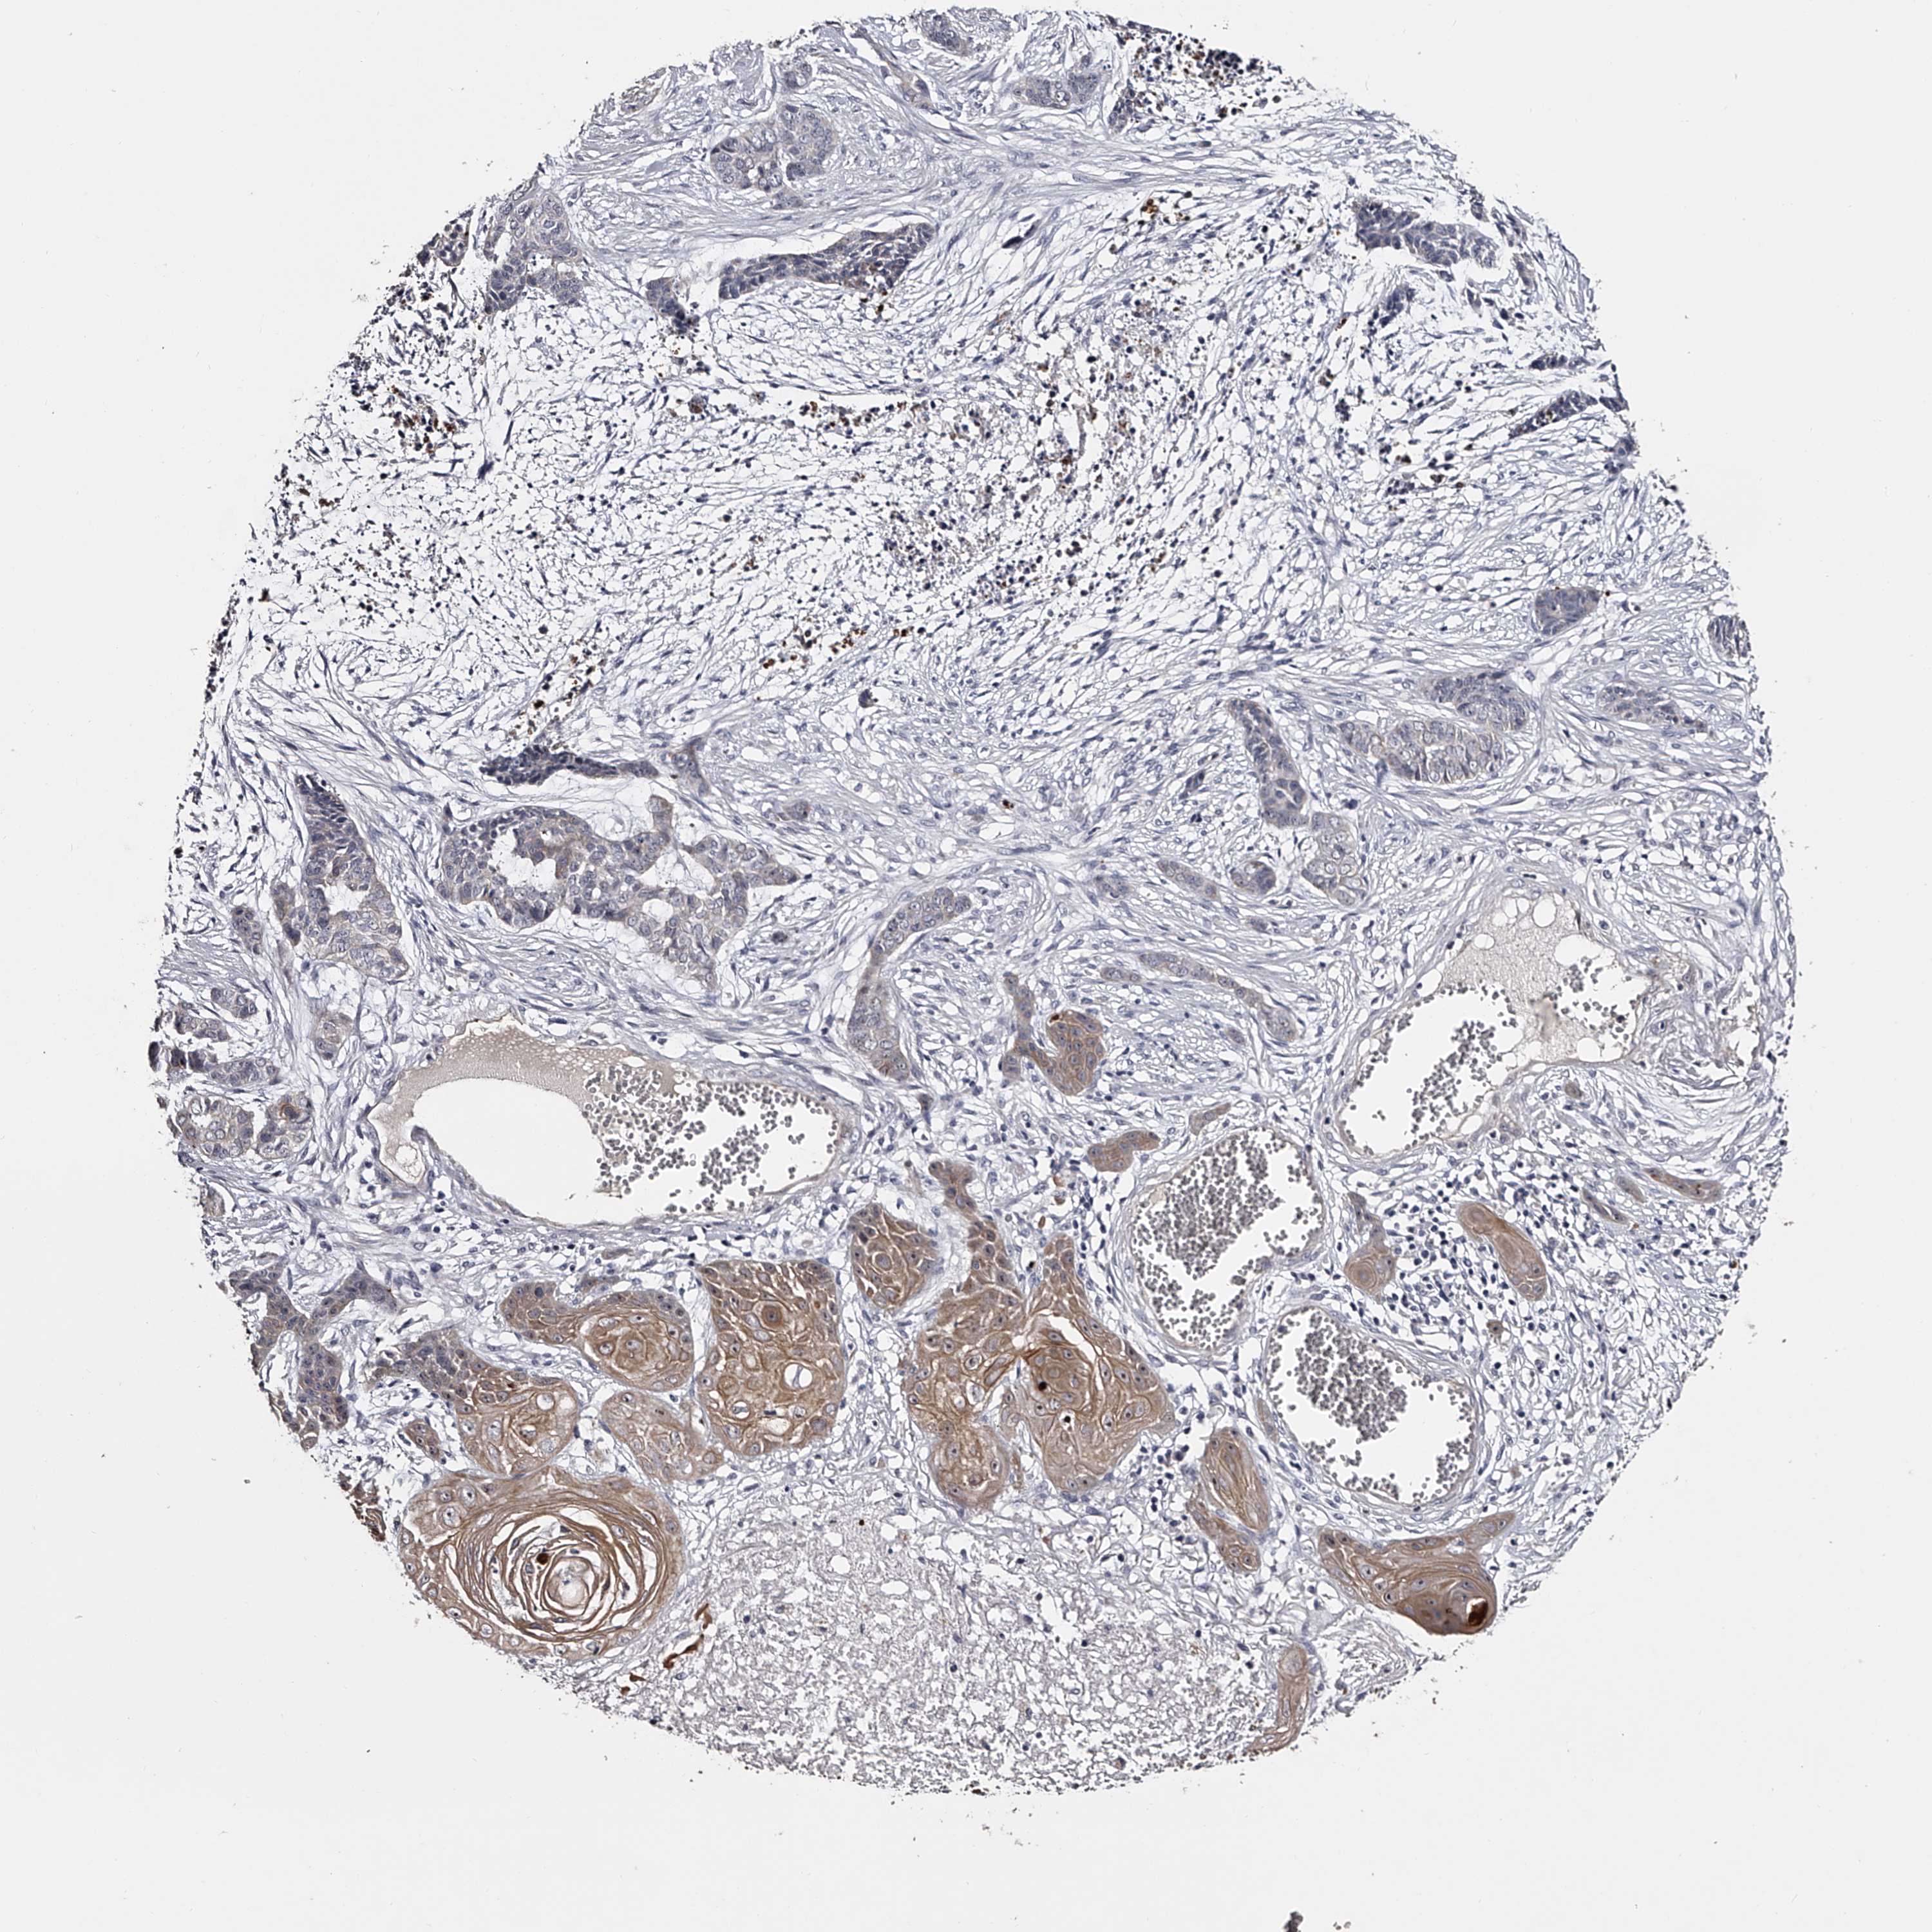

SKIN CANCER - Protein expressioni

A mouse-over function shows sample information and annotation data. Click on an image to view it in a full screen mode. Samples can be filtered based on level of antibody staining by selecting one or several of the following categories: high, medium, low and not detected. The assay and annotation is described here.

Each image is clickable and will lead to virtual microscopy that enables deeper exploration of all samples and also displays staining intensity scores, fraction scores and subcellular localization as well as patient and tissue information for each sample.

Antibody HPA029666

Antibody HPA029667

Antibody HPA029668

Antibody HPA029669

Basal cell carcinoma

Squamous cell carcinoma, NOS

Squamous cell carcinoma, metastatic, NOS